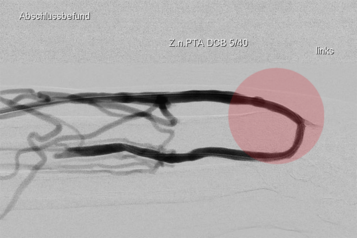

2. Angioplastie/ PTA – Gefäßweitung

Einengungen oder Verschlüsse von Gefäßen können durch Ballonkatheter beseitigt werden. Dazu werden die Ablagerungen in den Gefäßen zerteilt und in die Gefäßwand gedrückt, um so diese Stelle wieder zu glätten.

Neben sogenannten Normalballons kommen auch spezielle andere Arten von Ballonkathetern zur Anwendung. Dazu gehören u. a. Schneidballons oder Ballons die Stoßwellen abgeben, für sehr harte Gefäßablagerungen. Auch Ballonkatheter mit einer medikamentösen Beschichtung, die an die Gefäßwand abgegeben wird, um den arteriosklerotischen Gefäßumbau zu bremsen, werden eingesetzt.